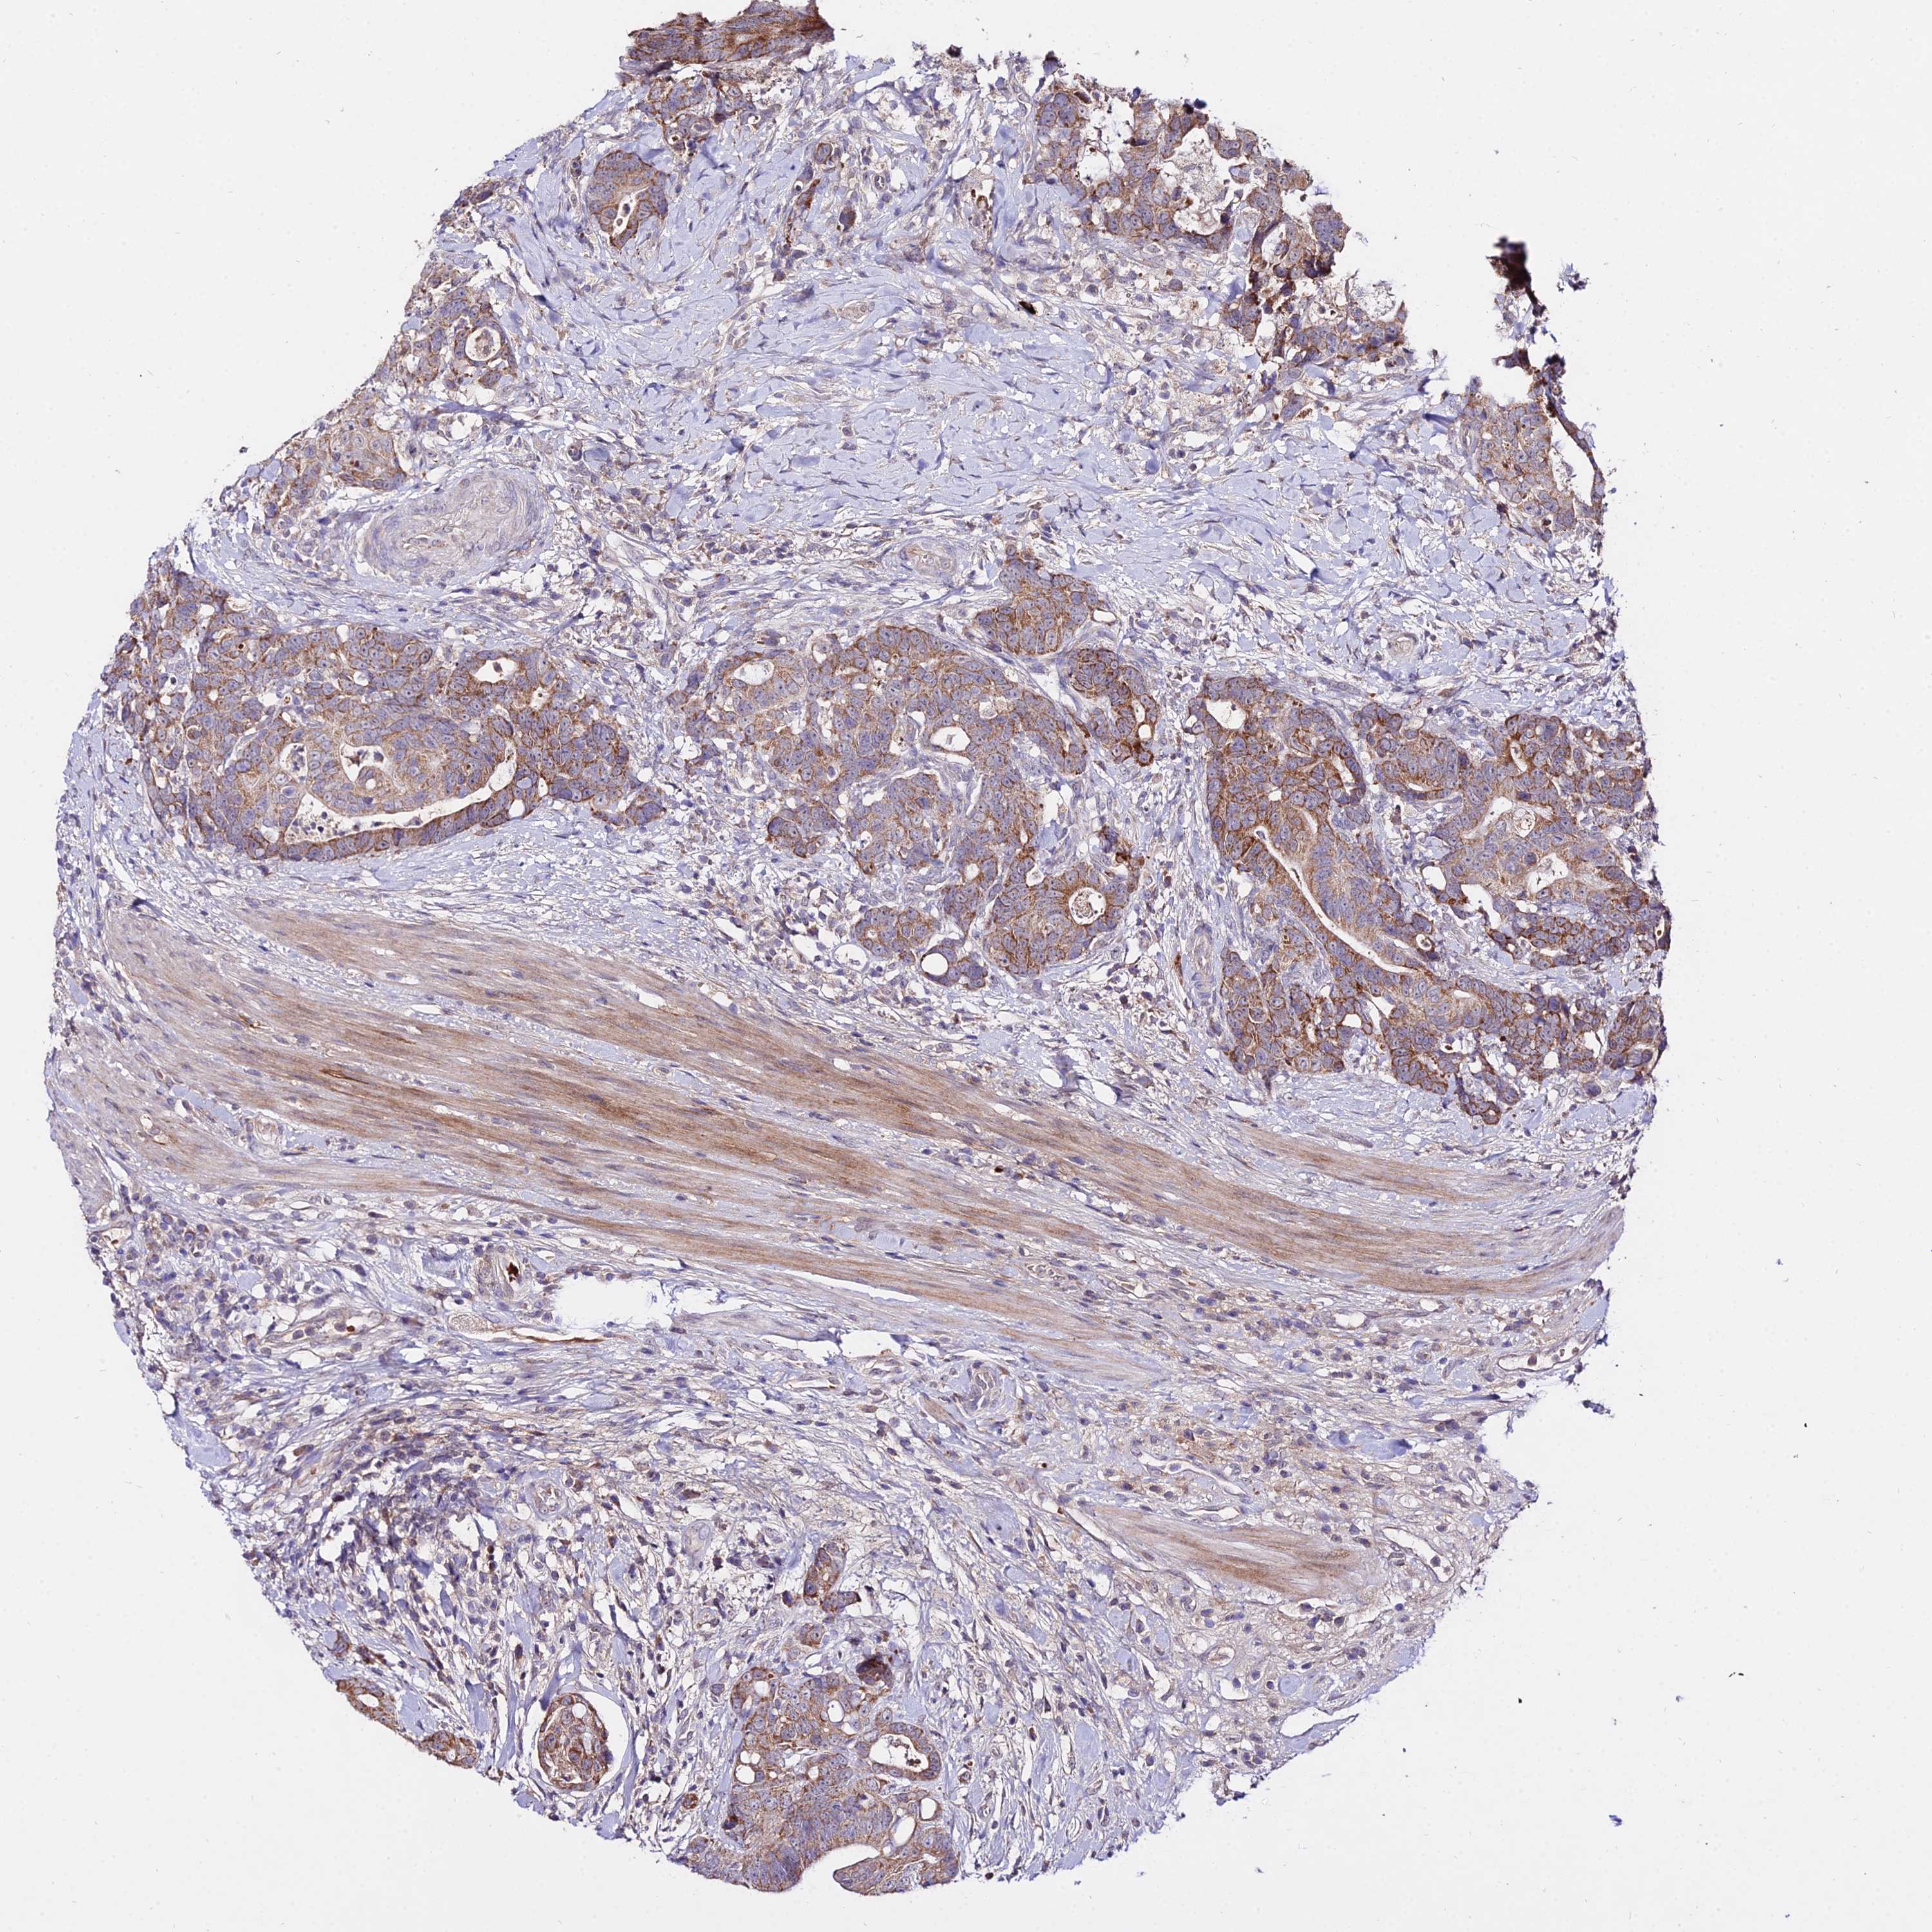

CANCER COLORECTAL CANCER Show tissue menu

Colorectal cancer

Human cancer

Rectum adenocarcinoma